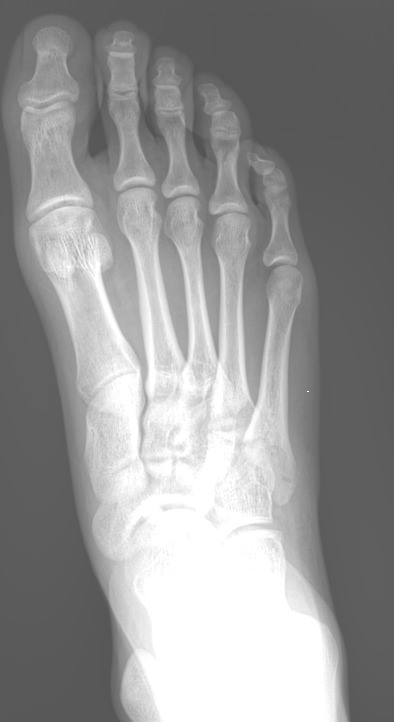

На снимке будут видны:

• Все суставные щели мелких суставов стопы и соответствие суставных поверхностей;

• Изменение в костной ткани и надкостнице;

• Целостность костей и суставов;

• Мягкие ткани стопы и отек в них;

• Новообразования.